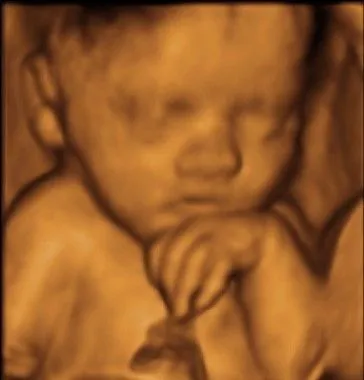

How about this, according to the soulless Democrat goons, this is nothing but a sack of cells that can be murdered at any time, if the mother so wishes.